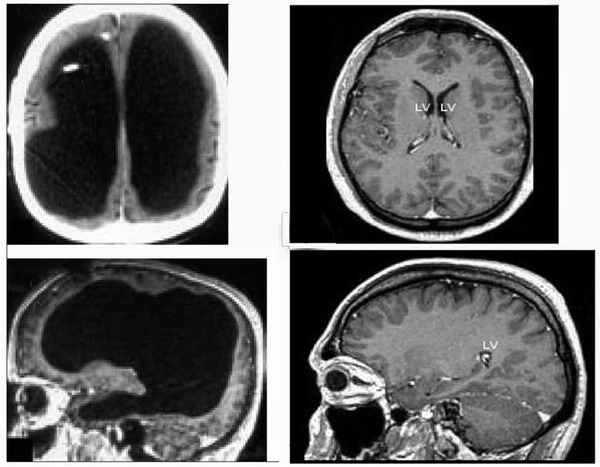

Французские врачи, сделавшие компьютерную и магнитно-резонансную томографию одному из пациентов, обнаружили, что большую часть полости черепной коробки занимают раздувшиеся от жидкости желудочки головного мозга, а сам мозг превратился в узкую полоску.

В голове сорокачетырехлетнего клерка из Марселя почти не оказалось мозгов: все темное пространство на фотографиях слева занято жидкостью. Для сравнения справа показан типичный человеческих мозг в тех же проекциях

44-летний мужчина обратился к врачам после того, как у него стала слабеть и плохо функционировать левая нога. Отмечается, что до этого он вел совершенно нормальное существование, работал на госслужбе, имел семью и двоих детей. Его IQ составлял 75 пунктов, ниже среднестатистических показателей в 100 пунктов, однако он не считался умственно отсталым. Подняв историю болезни, врачи обнаружили, что еще в детстве пациент страдал гидроцефалией – водянкой головного мозга. Ему был имплантирован внешний дренаж.

Однако, когда ему исполнилось 14 лет, дренаж почему-то сняли. Между тем ликвор продолжал накапливаться в боковых желудочках, постепенно оттесняя и сдавливая мозг. По словам врачей, они были удивлены, как человек многие годы мог спокойно существовать с диагнозом, практически несовместимым с жизнью. Обычно водянка ведет к повышению внутричерепного давления, которое сдавливает капилляры мозга, нарушению кровообращения и постепенной атрофии нервной ткани и как следствие к нарушению зрительных и двигательных функций. Однако, как предполагают медики, из-за того, что процесс расширения желудочков мозга указанного пациента проходил достаточно медленно, может быть на протяжении нескольких десятилетий, функции поврежденных областей мозга перешли к другим участкам.